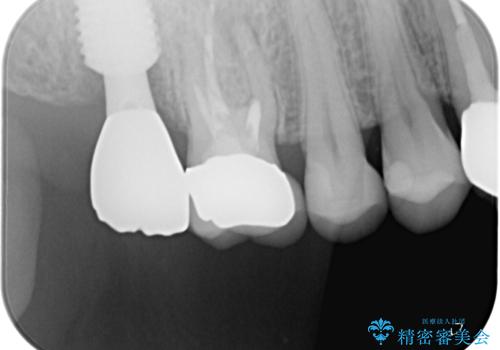

抜歯となった場合には、咬合力が強大であることと、嘔吐反射が強いため、処置の回数を極力減らし、速やかに咬合回復をさせることが望ましいと判断し、抜歯即時埋入・即時加重を前提とした処置を行うこととしました。

残念ながら歯冠から歯根に向かって破折が認められたため、患者様了解のもと、抜歯してインプラントの即時埋入を行いました。

インプラントと骨の安定程度を測定したところ、十分な数値が得られたため、速やかに仮歯を装着して咬合回復をさせることができました。